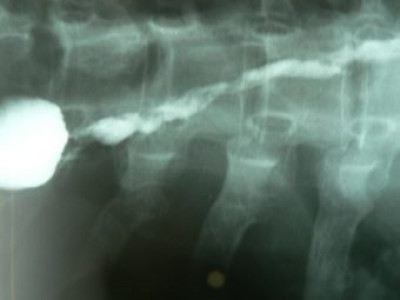

Dilatación esofágica con balón

Envíado por Dr. Carlos Miguel Zavaleta Consuegra